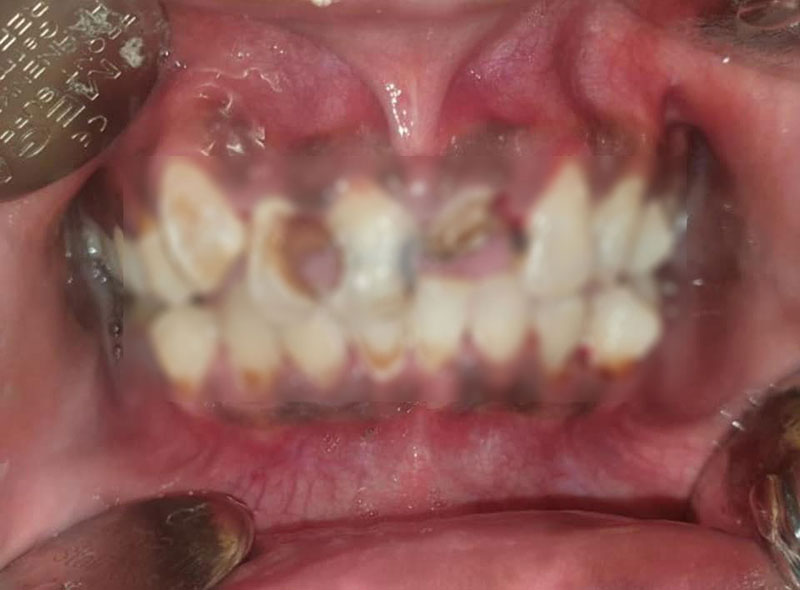

เมื่อตรวจช่องปากก็พบว่า เป็นเครื่องมือไม่ได้มาตรฐาน ส่งผลให้เกิดคราบสีขาว ซึ่งเป็นเชื้อราเกาะอยู่บริเวณเหงือกทั่วทั้งปาก จึงได้ทำความสะอาดและขูดหินปูน พร้อมกับสอนวิธีแปรงฟันอย่างถูกต้อง

ทั้งนี้ ยังพบว่า ฟันหน้า 2 ซี่ ของคนไข้ มีเชื้อแบคทีเรียลามลึกลงไปทะลุโพรงประสาทฟัน ทำให้มีหนอง จึงต้องถอนทิ้งทั้ง 2 ซี่ และทดแทนด้วยการทำฟันปลอมขึ้นมาให้กับคนไข้